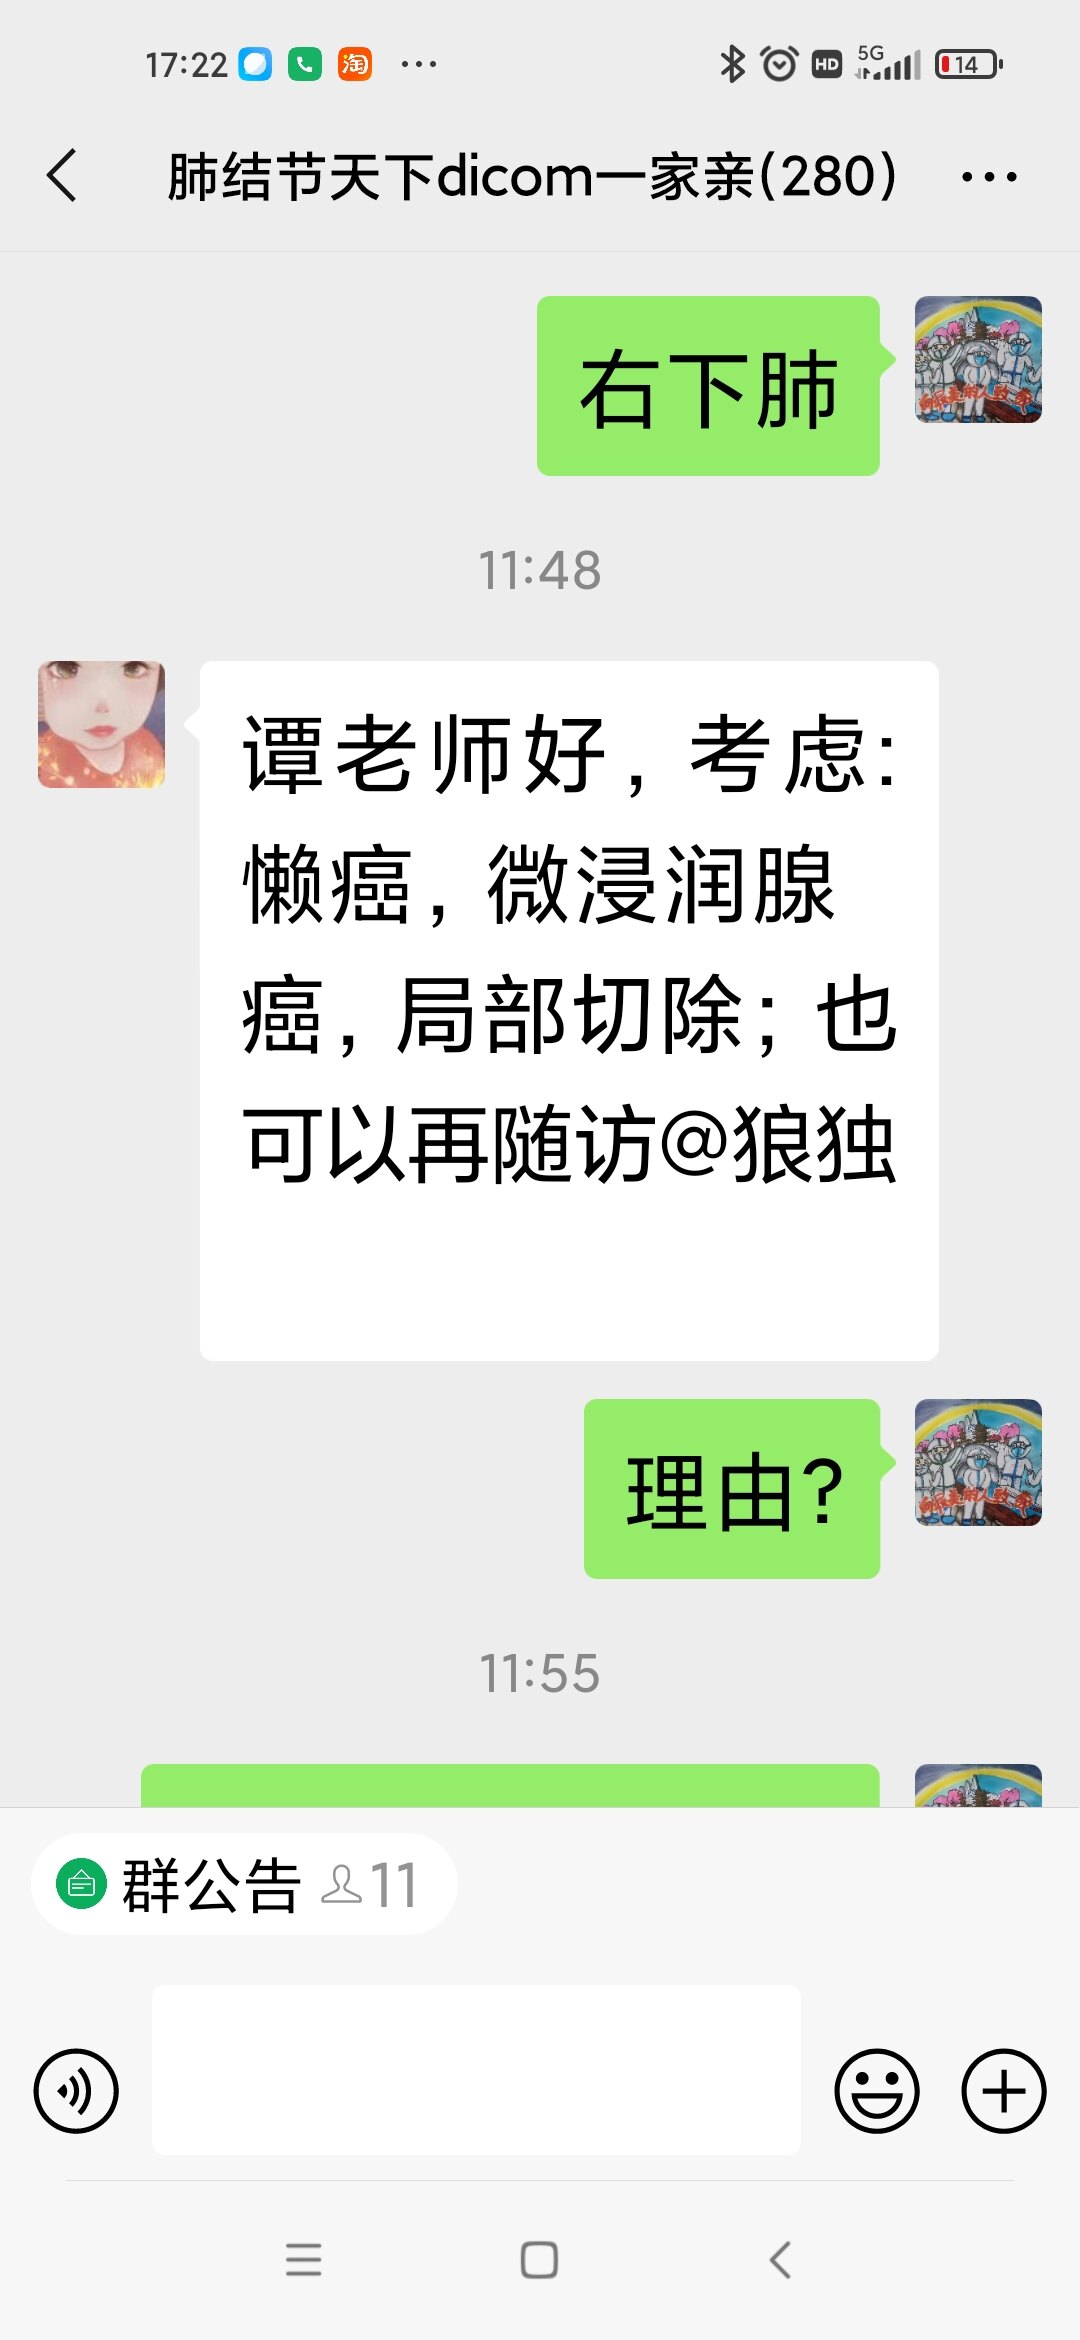

只言片语 之 (7)